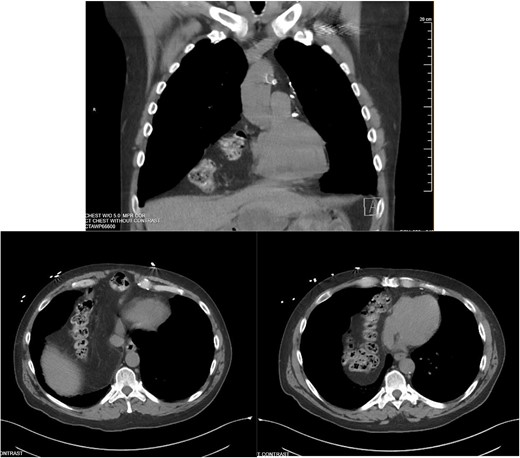

The falciform ligament was taken down with bipolar cautery. A peritoneal flap was created commencing about 4 cm inferior to the defect. A preperitoneal dissection was then performed to create the flap and to reduce the sac out of the mediastinum (Fig. 4).

Care was taken to avoid injury to the pleura and the pericardium. Once the sac was reduced, the defect’s size was measured as 9 cm in horizontal length by 4 cm in vertical dimension. Primary closure of the defect was performed with a running 0 V-loc absorbable 180 suture.